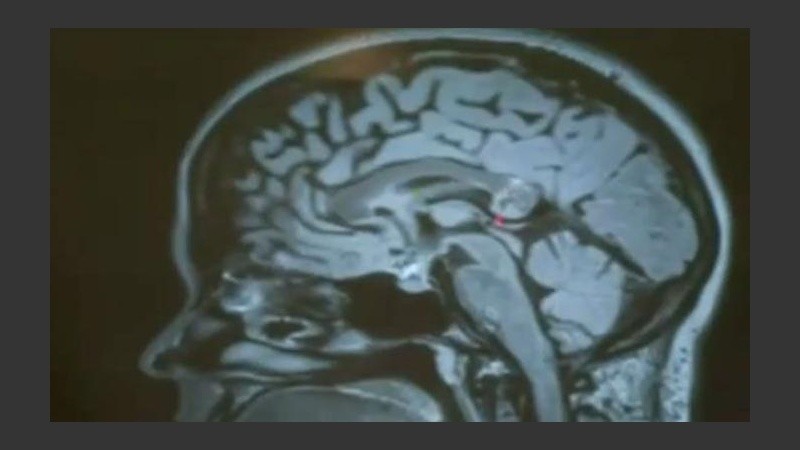

La mujer en cuestión se llama Yamini Karanam, quien se mudó a Indianápolis para estudiar informática. Al tiempo de su llegada comenzó a padecer fuertes dolores de cabeza, somnolencia y poca capacidad para concentrarse. Visitó, al menos, seis consultorios médicos que le indicaron que tenía un tumor cerebral que no podía operarse ya que estaba ubicado en un lugar donde corría riesgo su vida si se realizaba una cirugía.

Según informó NBC, compañeros de Yamini recaudaron 32 mil dólares para que la joven pueda hacer una consulta en Los Ángeles, donde un doctor le había diagnosticado que la masa que presionaba su cerebro no era un simple tumor, sino que era un teratoma.